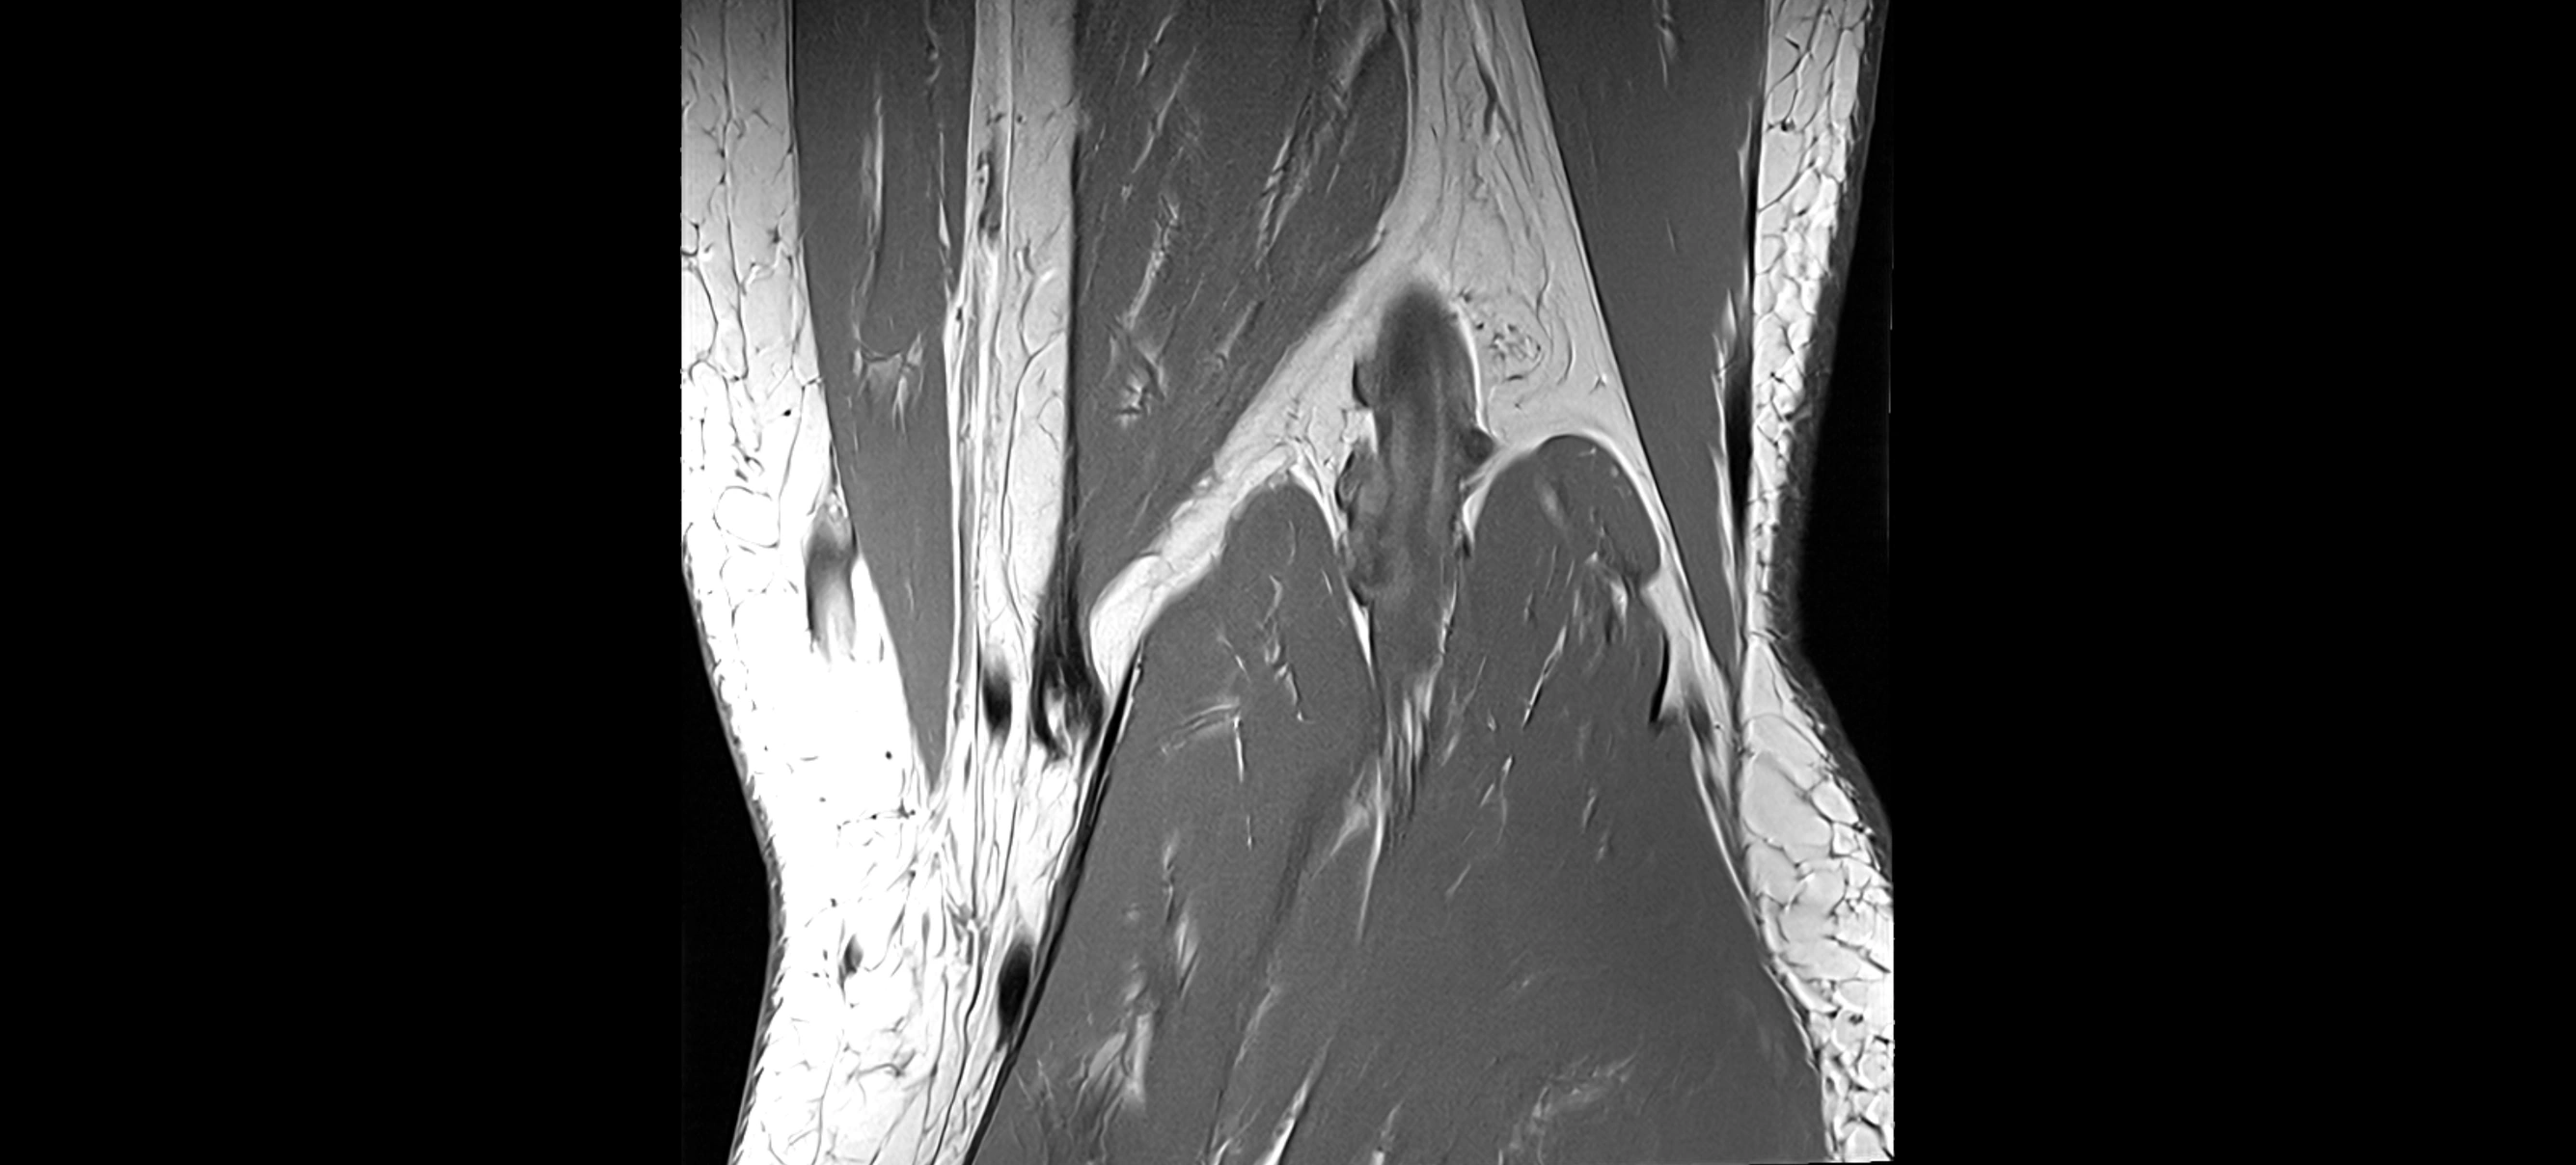

MRI images

image